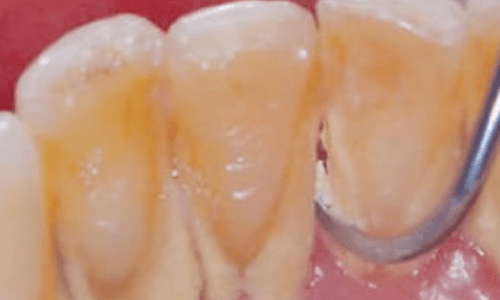

◆丁寧に歯石をプロが取り除きます。

歯茎

より上にできる歯石を「歯肉縁上歯石(しにくえんじょうしせき)」といい、歯茎より下にできる歯石を「歯肉縁下歯石(しにくえんかしせき)」といいます。

歯茎の上の歯石は歯のエナメル質表面にできるので、比較的除去しやすい歯石です。歯ぐきより下にできる「歯肉縁下歯石」は、歯と歯茎の間から染み出る浸出液とカルシウム成分が結び付き石灰化し固まってできた歯石です。褐色や黒っぽい色をしており、歯茎の下にこびりついているため、除去するのが難しいので少しづつ時間をかけて丁寧に取っていきます。